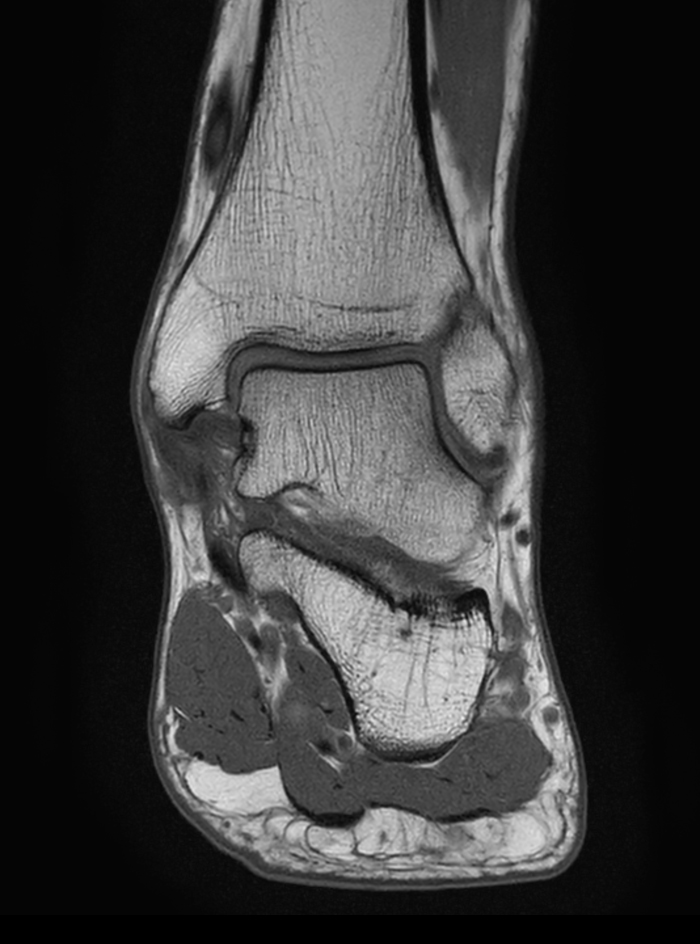

Ankle imaging with the dS 16ch FootAnkle coil

• Clinical Application